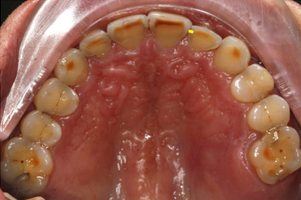

Mr NK, a 52-year-old male, presented with concerns of gradually shortening teeth and sensitivity to cold drinks. He also reported feeling self-conscious about his smile in photos. He is medically fit and has been using a night guard for his sleep-related grinding habit for the past year. Clinical examination revealed moderately worn dentition from erosion and attrition, along with mild crowding of the lower anterior incisors.

Intra-Oral Pictures (Before)

- Erosion severity: ACE Class Class III

- Reduced occlusal vertical dimension